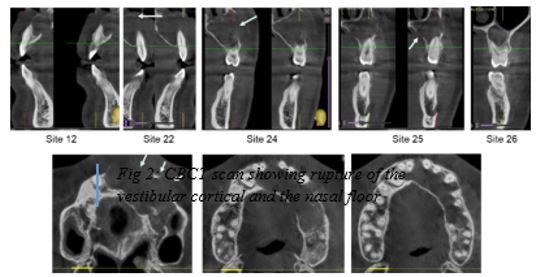

Figure 1 Panoramic radiograph: image of radiolucent cystic appearance, well limited, extended of 12 to 26.

Clinical examination revealed a mild, soft swelling in the left vestibular region without any signs of pain or infection, raising suspicion of vestibular cortical bone perforation. All teeth in the affected region were vital and free from caries. A fine needle aspiration was performed, yielding a whitish, caseous material rich in keratin, effectively ruling out an inflammatory cyst. Orthopantomogram imaging revealed a well-defined radiolucency extending from the maxillary incisor region to the contralateral right premolar-molar area.